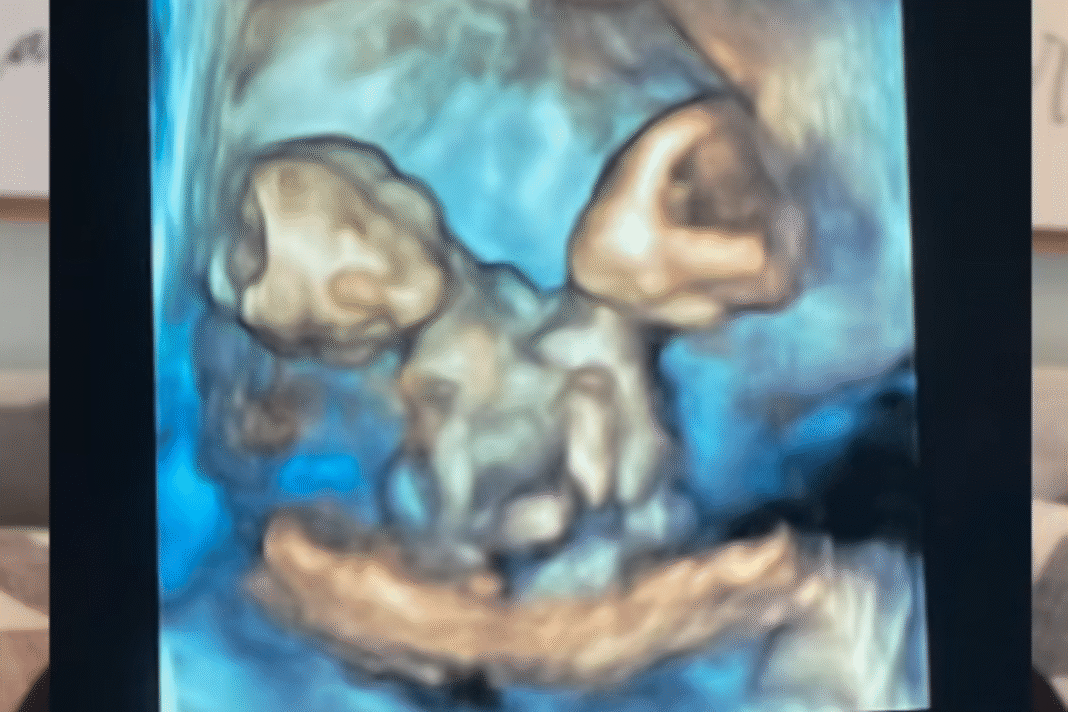

El técnico confirmó que Nicole, en ese momento, estaba embarazada del niño gemelo, pero estaban conectados a un corazón, hígado, intestino, diafragma y cordón de pulso.

Nicole dijo: “María deja un gran grito y Rachel estaba durmiendo durante todo el tiempo”. “Fue increíble ver sus pequeñas caras y su cuerpo compartido. Nunca había visto a los gemelos unidos antes, así que no puedo dejar de mirar a mis chicas y cómo se hicieron bajo mi corazón”.